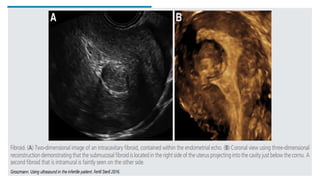

FIBROID

• 3D ultrasound has recently been

used to map the exact location of

fibroids in relation to the

endometrial cavity and

surrounding structures.

• This is extremely important in

triaging patients for surgery and

• Potentially useful in monitoring the

reduction in the size of fibroids in

patients receiving gonadotrophin-

releasing hormone analogs or

following uterine artery

embolization.

ENDOMETRIAL POLYPS

- Assessing whether or not a

patient has an endometrial

polyp and then determine the

size of the polyp and its pedicle.

-Studies have demonstrated that

the uterine cavity, endometrial

lining and myometrium are best

visualized using

sonohysterography, and that

these images are further

improved by the use of 3D

ultrasound.